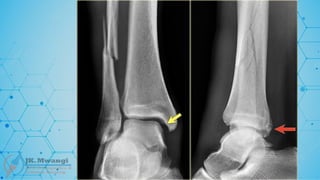

Potts fracture

 A fracture of the lower end of the fibula, often associated with damage to the

ligaments and dislocation of the ankle. Named after Percivall Pott, an English surgeon,

in the 18th century

Maisonneuve fracture

 A spiral fracture of the proximal third of the fibula associated with an ankle injury,

typically a disruption of the syndesmosis. Named after Jules Germain François

Maisonneuve, who described it in 1840.